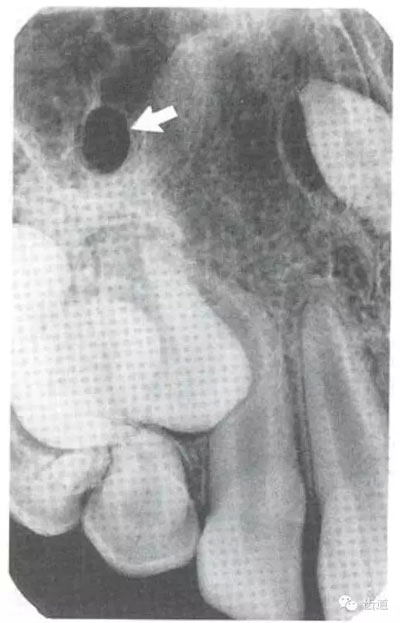

3)頦孔:

位于前磨牙根尖區(qū)域,為一大致圓形密度低的影像。頦孔位置變異大,多位于第二前磨牙根尖稍下,注意與根尖周病變區(qū)別,其要點是牙周膜及其骨硬板是否連續(xù)不斷。